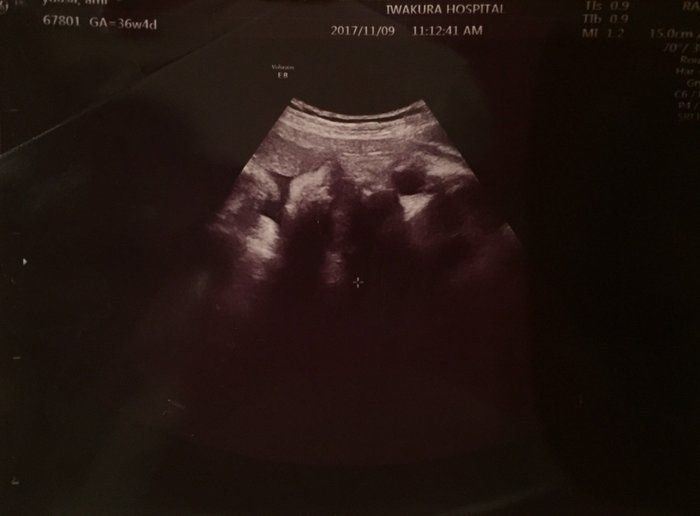

2度“逆子”になった胎児はもう小学生!子どもと共に読み返した当時の日記&エコー画像 -

「背骨!足骨!ホントに人間がいる!」エコー画像を見る度、ゆっくり親になっていく私たち -

おなかの中はどうなっていくの? エコー写真で振り返る、高齢ママのはじめての妊娠生活 -

エコー写真がある時代に、出産できて良かった!おなかにいる時から“赤ちゃんはかわいい” -